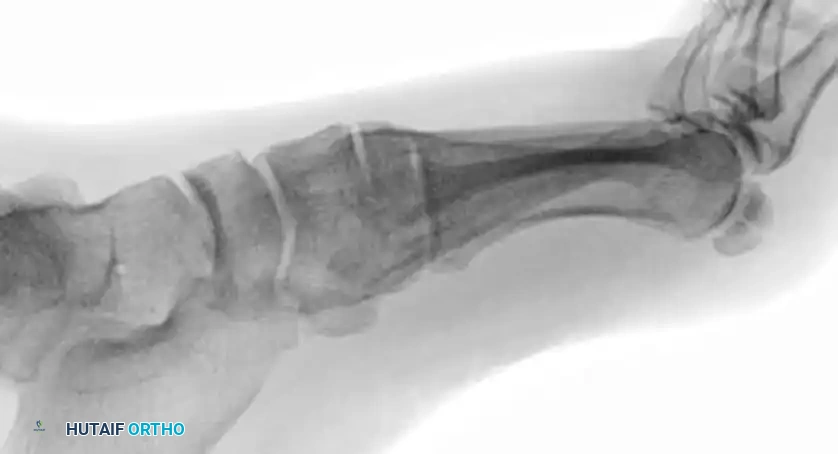

- Type A (Total Incongruity): Displacement of all five metatarsals, with or without a fracture of the second metatarsal base. Displacement is typically lateral or dorsolateral, moving as a single unit (homolateral).

- Type B (Partial Incongruity): One or more articulations remain intact.

- Type B1: Medial displacement, often involving the intercuneiform or naviculocuneiform joint.

- Type B2: Lateral displacement, which may involve the first metatarsal-cuneiform joint.

- Type C (Divergent): The first metatarsal displaces medially while the lesser metatarsals displace laterally.

- Type C1: Partial divergent.

- Type C2: Complete divergent. These are high-energy injuries associated with massive soft tissue swelling and a high risk of compartment syndrome.